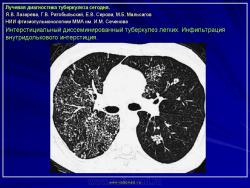

Лучевая диагностика туберкулеза сегодня

Я.В. Лазарева, Г.В. Ратобыльский, Е.В. Серова, М.Б. Мальсагов

НИИ фтизиопульмонологиии ММА им. И.М. Сеченова